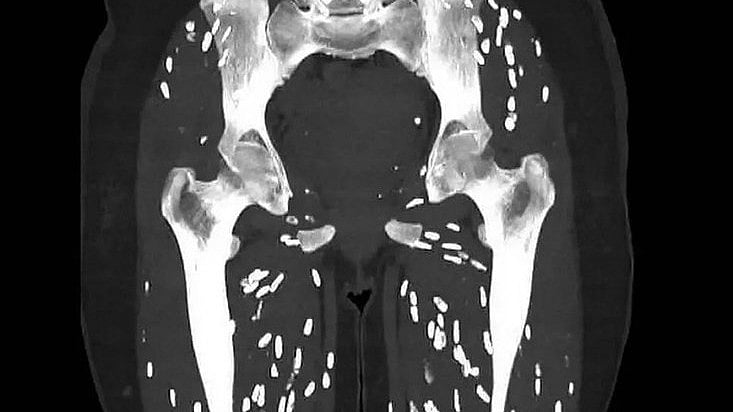

Ghali shared the unsettling picture of the CT scan showing a person's lower limbs filled with rice grain like particles and captioned it, "Here’s one of the craziest CT scans I’ve ever seen."

Ghali further went on to explain what the disease is called and what are its causes. "Cysticercosis is an infamous parasitic infection caused by ingestion of larval cysts of Taenia Solium, also known as: Pork Tapeworm," he wrote in the post.

According to the doctor, after the eggs are ingested (humans or pigs) they release larvae which penetrate the intestinal wall and invade into the bloodstream (via mesenteric venules) and from there can spread to literally anywhere in the entire body.

The main target of the parasite are the brain, eyes, subcutaneous tissues, and skeletal muscles.